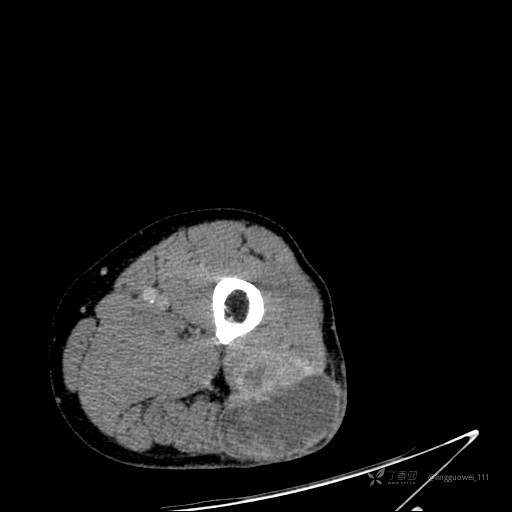

患者性别:男,85岁。发现大腿软组织肿块1年,增大3月,良性还是恶性?只有CT,能诊断正确吗?

静脉期: